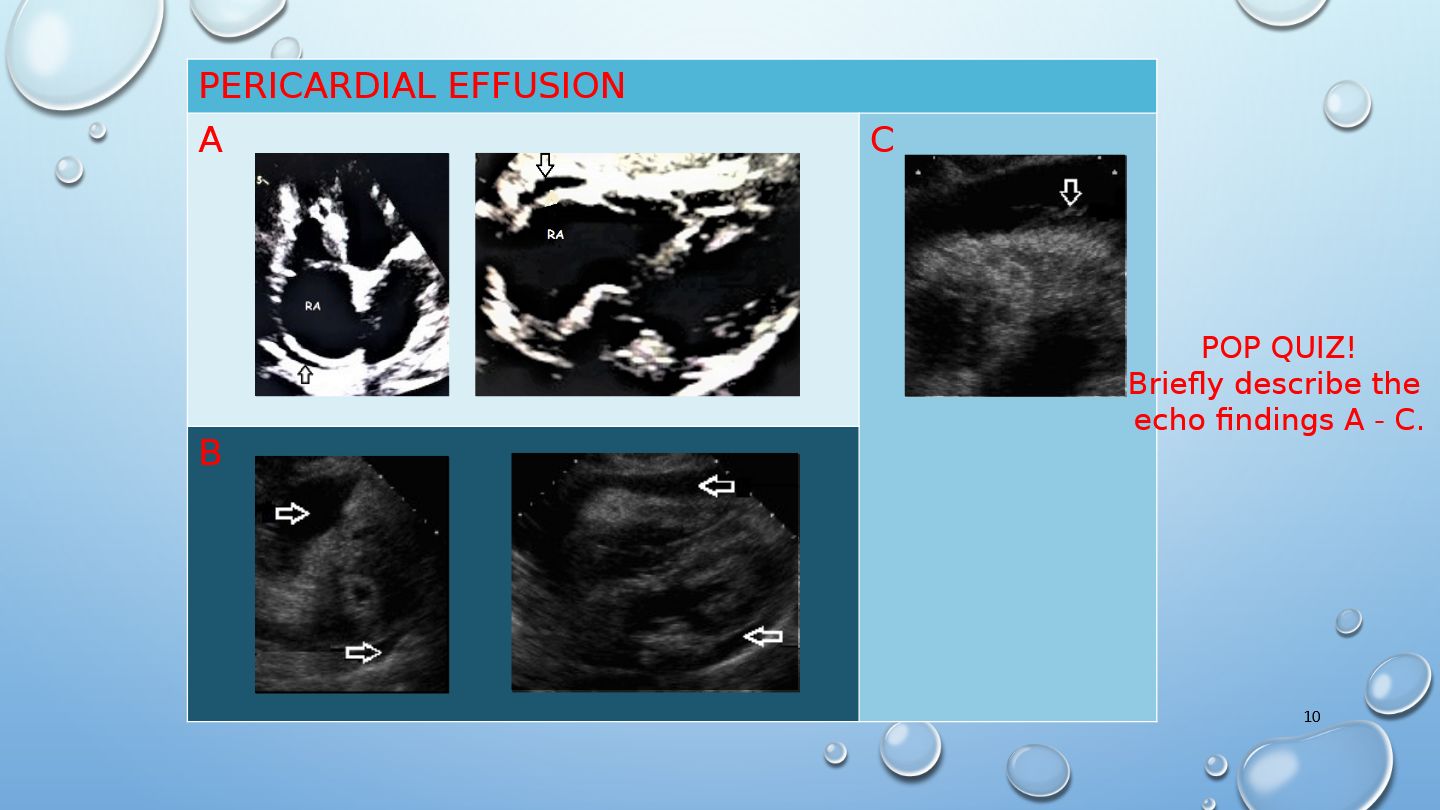

Which echocardiographic findings are most indicative of cardiac tamponade?

Pericardial effusion, RV diastolic collapse, and dilated hepatic veins